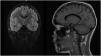

Se descarta edema de papila y se completa estudio con TC y RM cerebral (fig. 1). Por imagen se plantea, como principal sospecha diagnóstica, glioma difuso de línea media, sin poder descartarse patología inflamatoria. Por ello se completa estudio con RM con espectroscopia (RME), que no es concluyente para patología tumoral (fig. 2). Se retrasa biopsia quirúrgica y se solicita PET con metionina (no sugestiva de glioma de alto grado). Ante la sospecha de encefalitis autoinmune, se solicitan anticuerpos anti-MOG/AQP4 (negativos), y se inicia corticoterapia sistémica intravenosa1.

A los 2 meses de tratamiento se objetiva desaparición de sintomatología neurológica y mejoría radiológica importante, con resolución completa de la lesión a los 5 meses (fig. 3), confirmándose la etiología inflamatoria.